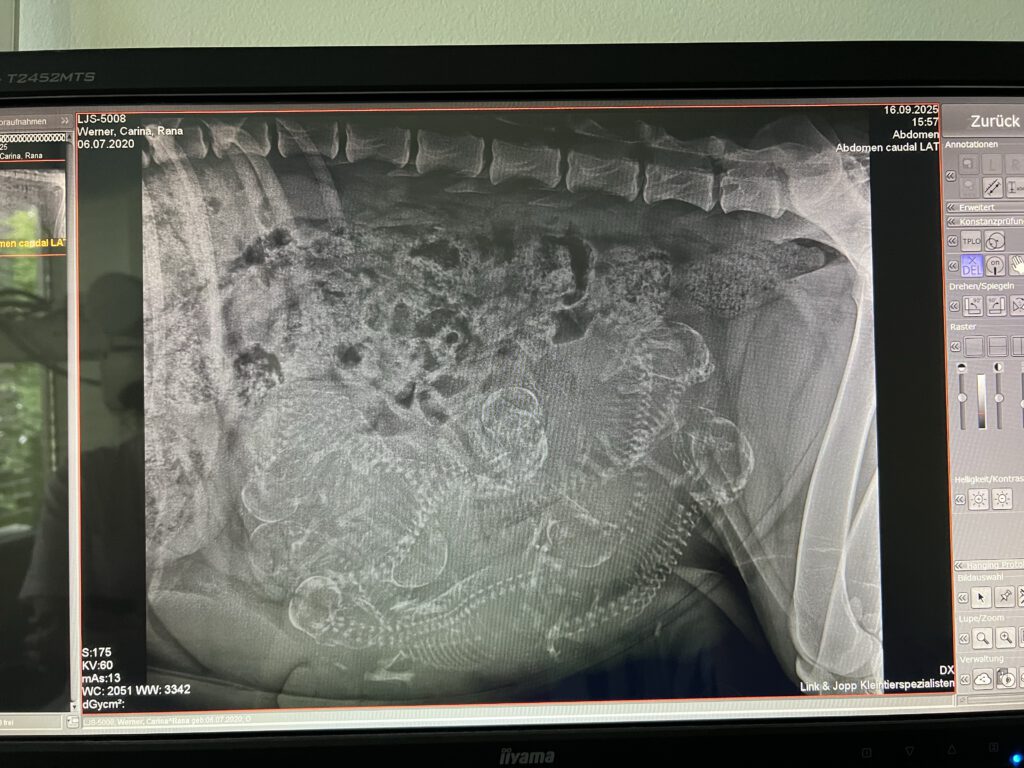

Wahengas und Ranas Sommer-Liaison trägt Früchte.

Seit Mitte August warten wir gespannt und geduldig auf die Ankunft unserer Bravehearts.